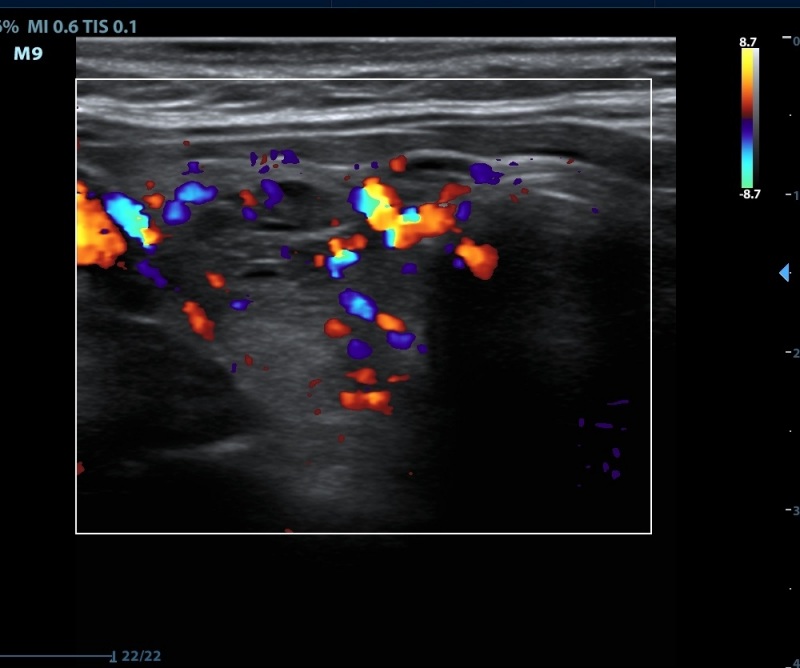

Ultrasonography. The thyroid was echonormal. There were numerous discrete lesions in the right lobe. There was a dominantly solid, echonormal nodule in the isthmus and an almost completely cyst in the left lobe.